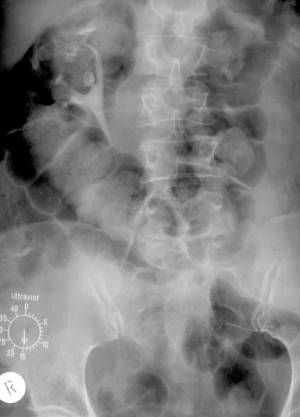

Fig. 58 – Ectopie bilaterala, lombara dreapta si presacrata stanga (vezica cu amprenta uterina pe conturul superior)